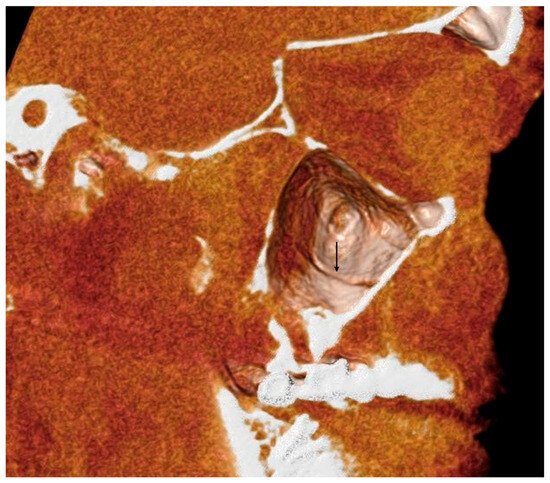

- The height of the maxillary bone crest in the cranio-caudal direction, on cross-section at the level of the first superior molar (Figure 3);

- The sized branches of the alveolar antral artery at the level of the first superior molar.